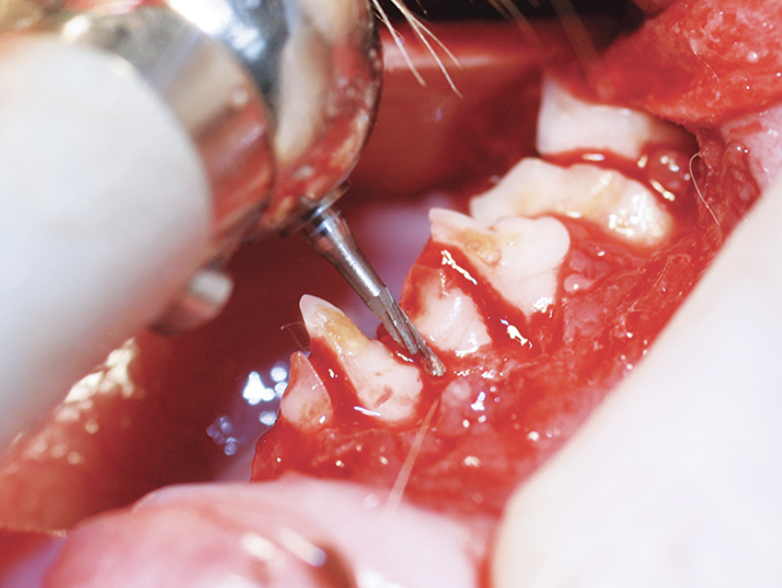

Los pacientes con mucositis caudal en el área delimitada medialmente por los pliegues palatoglosos y las fauces (antes denominada faucitis, que es menos precisa) generalmente no responderán al tratamiento de Fase I; A menudo se recomienda la intervención de fase II (es decir, extracciones de la boca caudal, extracción completa de todos los premolares y molares restantes y desbridamiento de los tejidos inflamados [p. Ej., Márgenes gingivales friables y crestas alveolares]). Los incisivos también se pueden quitar, pero, a menos que haya una inflamación significativa o pérdida ósea, los dientes caninos se conservan debido al tiempo quirúrgico adicional y al gasto requerido para las extracciones de boca completa y / o la preferencia del propietario para preservar los caninos.